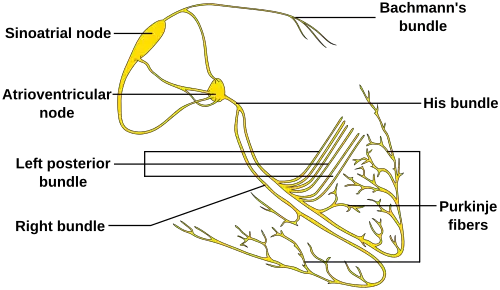

The sinoatrial node (SA node) is the primary pacemaker of the heart. It is a region of cardiac muscle on the wall of the upper right atrium near to the superior vena cava entrance. The cells that make up the SA node are specialized cardiomyocytes known as pacemaker cells that can spontaneously generate cardiac action potentials. These signals are propagated through the heart's electrical conduction system.[1][2] Only one percent of the heart muscle cells are conductive, the rest of the cardiomyocytes are contractile.

The SA node controls the rate of contraction for the entire heart muscle because its cells have the quickest rate of spontaneous depolarization, thus they initiate action potentials most quickly. The action potential generated by the SA node passes down the electrical conduction system of the heart, and depolarizes the other potential pacemaker cells at the AV node to initiate action potentials before these other cells have had a chance to generate their own spontaneous action potential, thus they contract and propagate electrical impulses to the pace set by the cells of the SA node. This is the normal conduction of electrical activity in the heart.

Impulses from the sinus node reach the atrioventricular node which acts as the secondary pacemaker. The cells of the AV node normally discharge at about 40–60 beats per minute.

The atrioventricular node and the Bundle of His, a little further down, are located in the region separating the atria from the ventricles known as the atrioventricular junction. The Bundle of His transmits signals to the bundle branches, which send them on to the Purkinje fibers. These will also produce a spontaneous cardiac action potential at a rate of 30–40 beats per minute, so if the SA and AV node both fail to function, these cells can also become pacemakers but with a much lower rate of conduction than either the primary or secondary pacemakers.

If the SA node does not function, or the impulse generated in the SA node is blocked before it travels down the electrical conduction system, a group of cells further down the heart will become its pacemaker.[3] This center is typically represented by cells inside the atrioventricular node (AV node), which is an area between the atria and ventricles, within the atrial septum. If the AV node also fails, Purkinje fibers are occasionally capable of acting as the default or "escape" pacemaker.